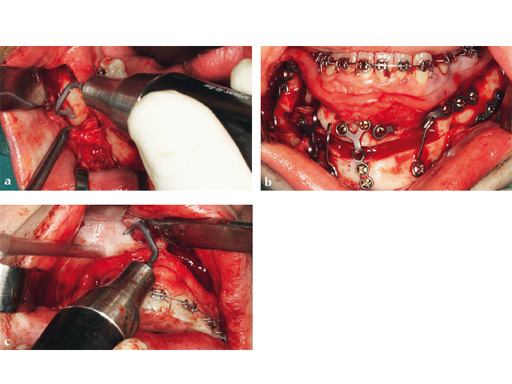

Case 2: Complex congenital deformity with distortion of alveolar processes and dentition, resulting in a 3.5 cm nonocclusion in the right maxillomandibular complex. Occlusion is exclusively controlled through the left second premolar to second molar. Piezosurgery was useful in this case due to complex anatomical deformities resulting in atypical positioning of the inferior alveolar canal on the right side. The cramped confines of dental and bony tissues in the deformed anatomy required an adequate type of osteotomy to do a significant yet controlled skeletal movement to overcome the vertical discrepancy intraorally, without changing the outer projection of the mandibular frame.

Case provided by Nils-Claudius Gellrich, Hannover, Germany